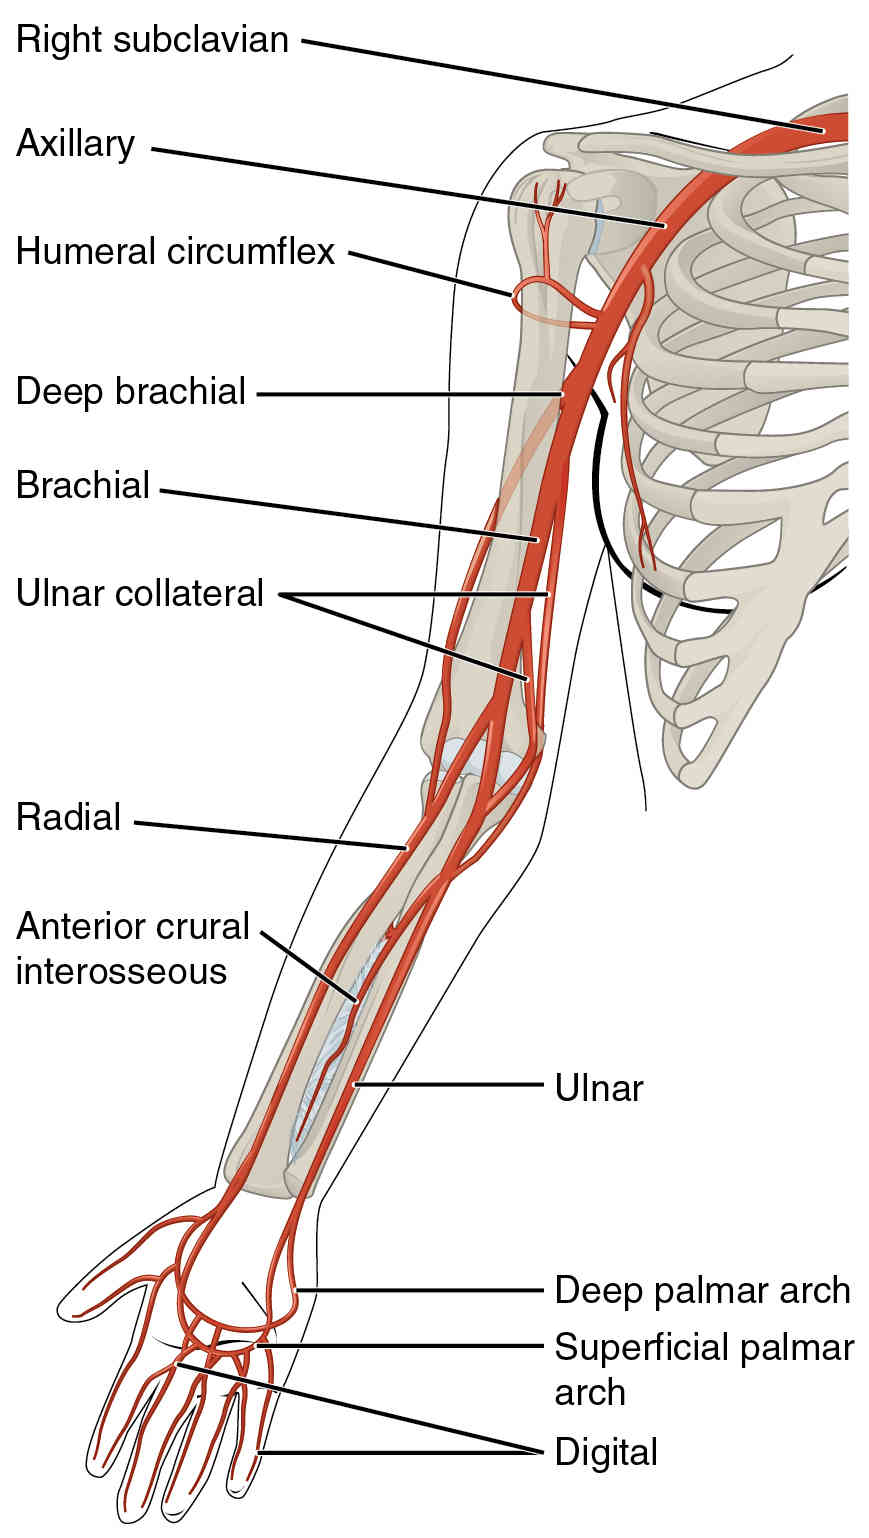

This page is under construction. For now, it is just a resource of the images found in the OpenStax Anatomy and Physiology Handbook. It wil slowly change into a revision tool. Each slide has a number. Use this to refer to the slide. When completed, it will have an unlabelled section, with labelled slides in parallel. On the unlabelled slides, write your answer and use the labelled slide to assess yourself. Keep track by also noting the number on each slide. Improvement at each attempt is important, more so than full marks on a first attempt.